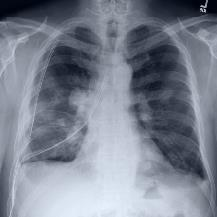

Thoracic disease detection from chest radiographs using deep learning methods has been an active area of research in the last decade. Most previous methods attempt to focus on the diseased organs of the image by identifying spatial regions responsible for significant contributions to the model's prediction. In contrast, expert radiologists first locate the prominent anatomical structures before determining if those regions are anomalous. Therefore, integrating anatomical knowledge within deep learning models could bring substantial improvement in automatic disease classification. This work proposes an anatomy-aware attention-based architecture named Anatomy X-Net, that prioritizes the spatial features guided by the pre-identified anatomy regions. We leverage a semi-supervised learning method using the JSRT dataset containing organ-level annotation to obtain the anatomical segmentation masks (for lungs and heart) for the NIH and CheXpert datasets. The proposed Anatomy X-Net uses the pre-trained DenseNet-121 as the backbone network with two corresponding structured modules, the Anatomy Aware Attention (AAA) and Probabilistic Weighted Average Pooling (PWAP), in a cohesive framework for anatomical attention learning. Our proposed method sets new state-of-the-art performance on the official NIH test set with an AUC score of 0.8439, proving the efficacy of utilizing the anatomy segmentation knowledge to improve the thoracic disease classification. Furthermore, the Anatomy X-Net yields an averaged AUC of 0.9020 on the Stanford CheXpert dataset, improving on existing methods that demonstrate the generalizability of the proposed framework.